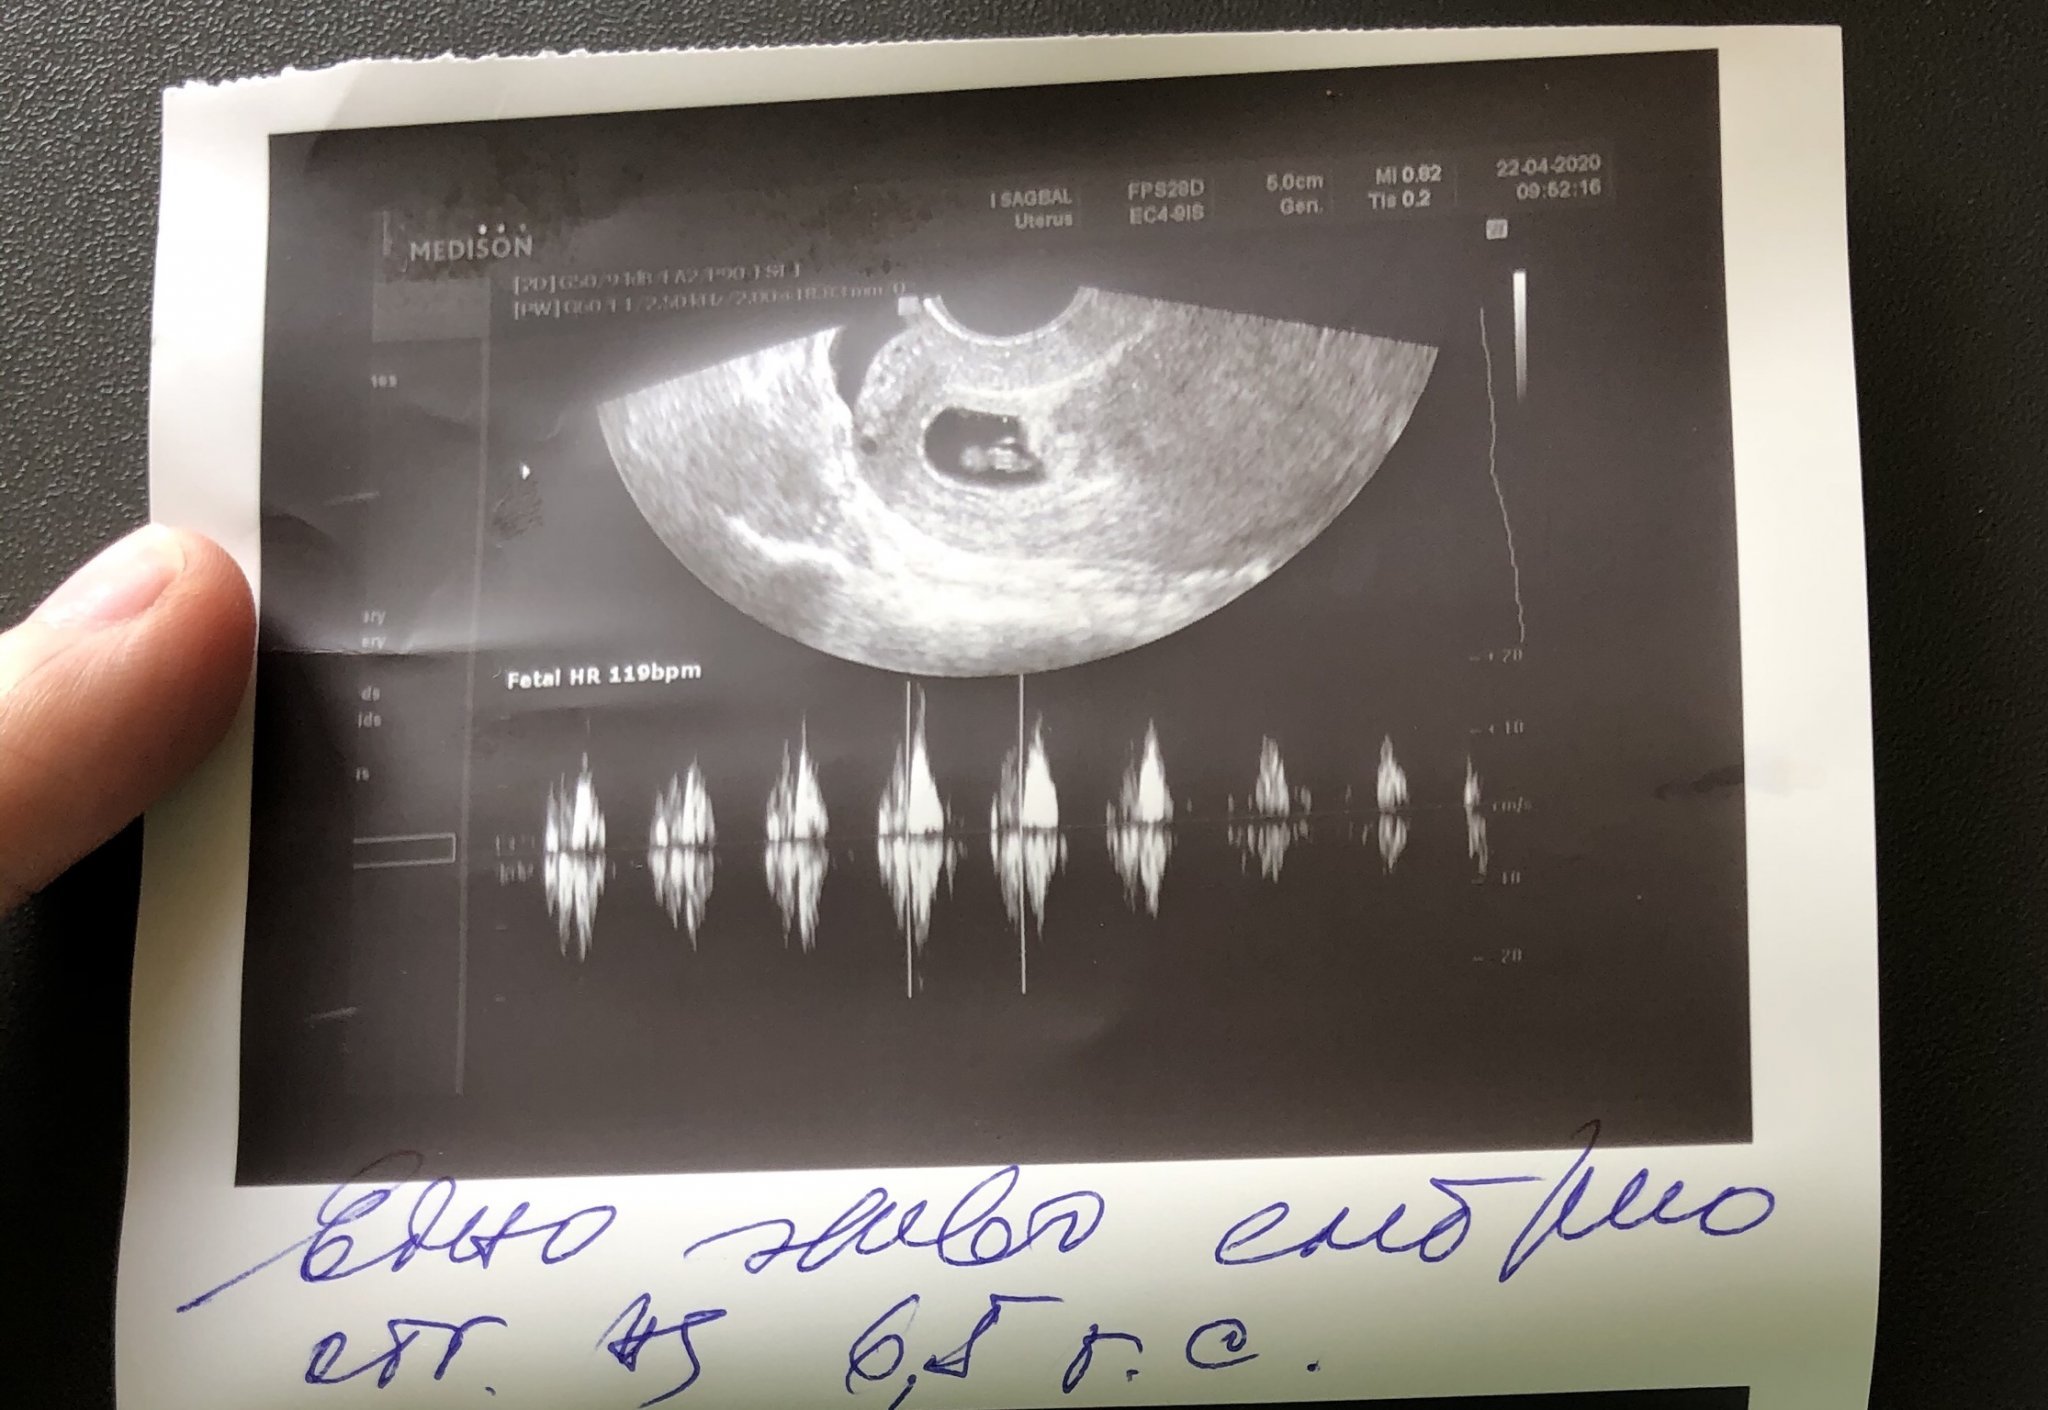

Основните теми в дискусията се въртят около опитните зачевания, бременността и подготовката за нея. Участниците споделят своите лични истории, преживявания и си оказват взаимна подкрепа по време на процеса. Дискусията обхваща теми като бременност, опити за зачеване, подкрепа и споделяне на лични истории, преживявания и емоции, свързани със зачеването и бременността.

Участниците се сблъскват с трудности като физически дискомфорт, емоционални предизвикателства и стрес по време на опитите за зачеване. Те търсят подкрепа и споделят съвети как да се справят с тези трудности. Участниците също така се сблъскват с предизвикателства като спонтанни аборти, проблеми с овулацията, тромбофилния синдром, нередовния менструален цикъл, положителните и отрицателните резултати от тестовете за бременност и емоционалните трудности, свързани с процеса на зачеване.